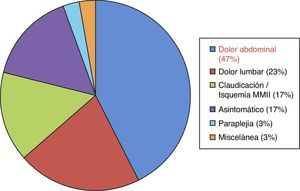

Su etiología es variable: espontánea, traumática, iatrogénica. A día de hoy la más frecuente es de origen idiopático o espontáneo (fig. 3). La clínica es poco específica, pero conjuntamente con los factores de riesgo nos ayudará ante la sospecha de dicho cuadro. Así puede cursar con: dolor abdominal y/o torácico, cuadros isquémicos a diferente niveles, y en un porcentaje nada desdeñable, el cuadro clínico es asintomático (17%)2 (fig. 4). El diagnóstico de confirmación se realiza en más de la mitad de los casos mediante angio-TAC (75%), aunque también se puede realizar a través de estudios ecográficos, angiográficos o con angio-RM5.